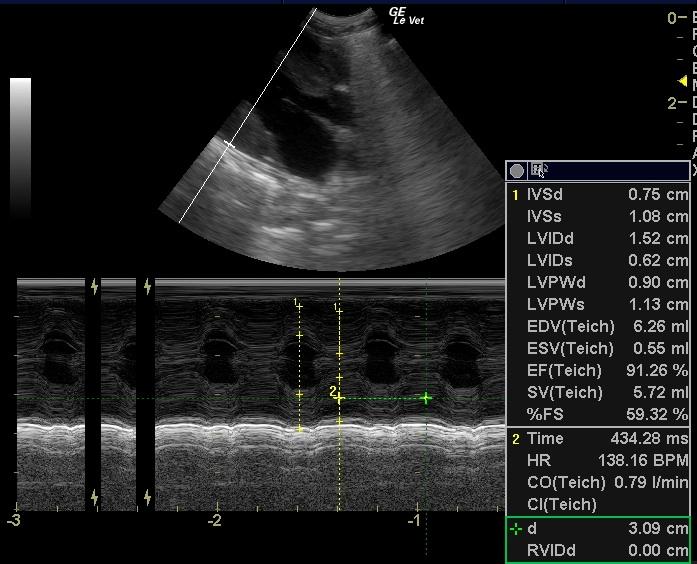

A 1-year-old intact male DSH was presented for anorexia over a 1-2 day period. Abnormalities on physical examination included hypothermia, a grade IV/VI systolic murmur, and ataxia. Leukocytosis was present on CBC. On survey radiographs, the intestines appeared to be bunched.